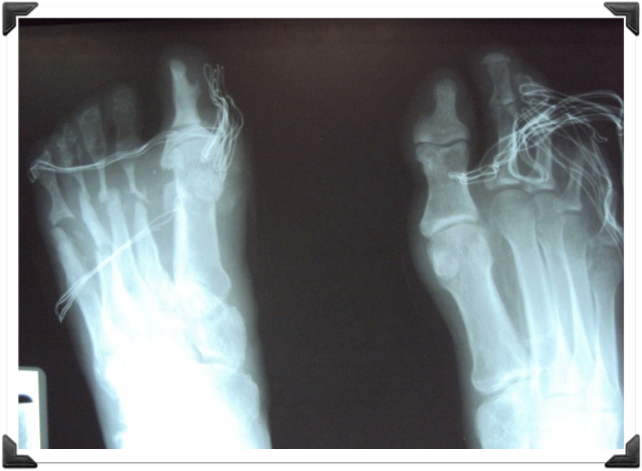

Rx Pre Operatorias

Cabeza del 2do MTT deformidad en flexion

Fusion Interfalangica de 2,3,4 y 5to Dedos